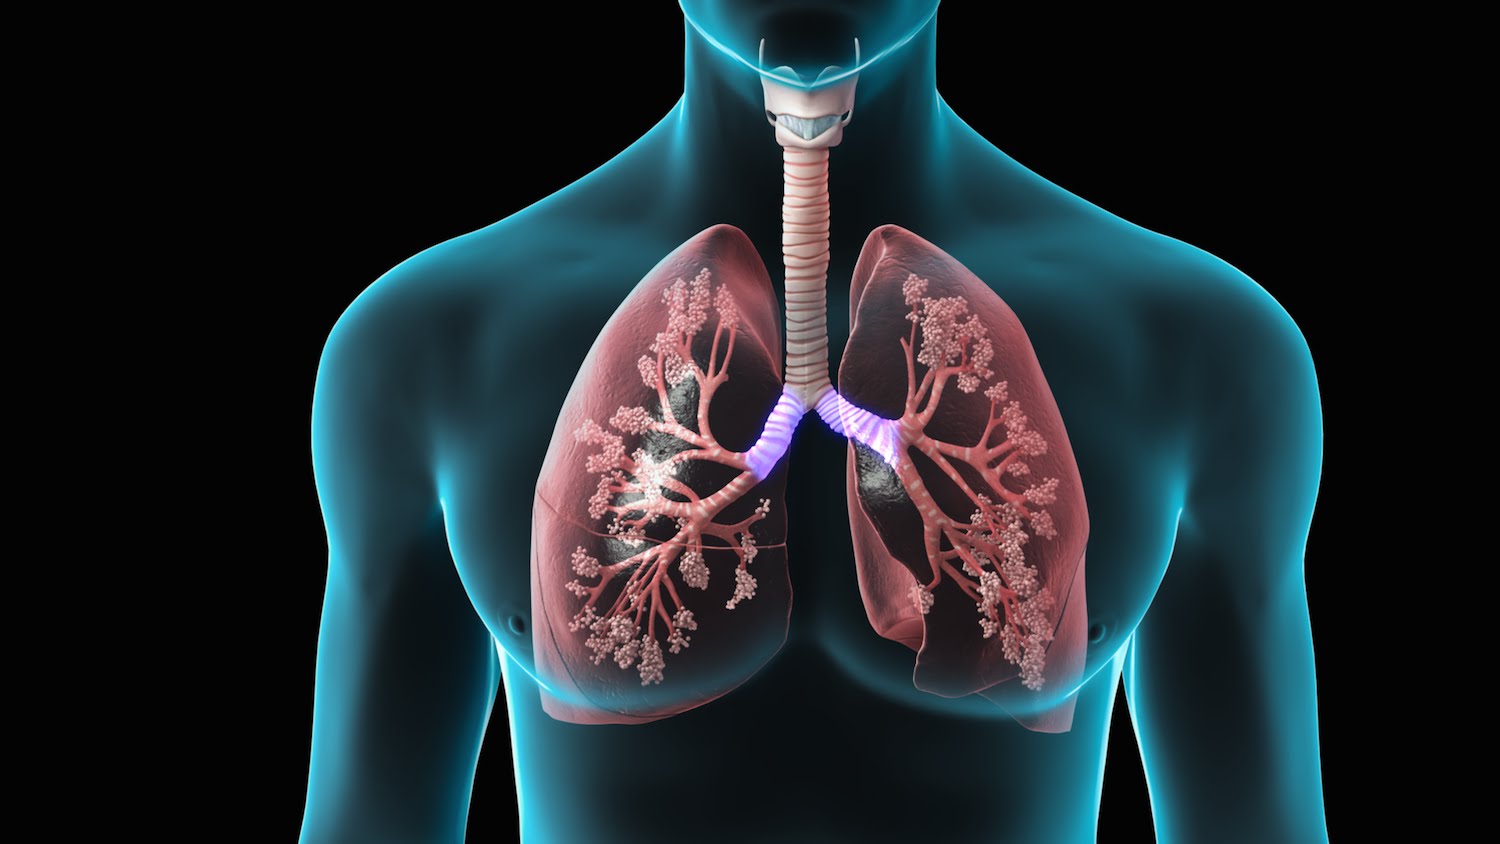

Lungenkrebs; Eine Krankheit, die sowohl Raucher als auch Nichtraucher einfängt

In den Jahrzehnten ist Krebs zu einer der Hauptursachen für Todesfälle geworden. Von 8 großen Krebsarten ist Lungenkrebs eine der am häufigsten verbreiteten Krebs, die jedes Jahr die maximale Anzahl von Menschen tötet, die sowohl Männer als auch Frauen auf der ganzen Welt umfasst. Wir haben alle von Beispielen gehört, in denen Krebspatienten ausgehärtet sind. Die Zahl der von ihm sterbenden Personen steigt jedoch rasch an.

Lungenkrebs hat zwei Typen: nOn-Small-Cell-Lungenkrebs (NSCl) und kleiner Zell-Lungenkrebs (SCLC), der den Ärzten weiterhin hilft, das Ausmaß zu stillstehen, in dem Krebs bereits verbreitet ist und wie es möglicherweise behandelt werden kann.

Die drei Arten

Die American Cancer Society (ACS) erklärt "Nicht-Small Cell Lung Cancer (NSCLC) -Krebserkrankungen für etwa 80 Prozent der Lungenkrebsfälle. Die drei Hauptgeräte von NSCLC sind:

-Adenokarzinom. Dies macht 40 Prozent der Fälle von Lungenkrebs aus. Es ist normalerweise in den äußeren Teilen der Lunge zu finden. Es neigt dazu, langsamer zu werden als die beiden anderen Subtypen, so dass es eine bessere Chance gibt, einen Tumor zu finden, bevor er sich verbreitet hat.

-Plattenepithelkarzinom. Dies macht etwa 25 bis 30 Prozent der Lungenkrebserkrankungen aus. Es wächst aus den Zellen, die die Innenseiten der Lungen-Atemwege leiten. Das Plattenepithelzellkarzinom wird normalerweise in der Mitte der Lunge gefunden.

-Large Zellkarzinom. Dies macht 10-15 Prozent der Lungenkrebserkrankungen aus. Es ist in einem beliebigen Teil der Lunge zu finden, und neigt dazu, schneller zu wachsen als die anderen Subtypen. "